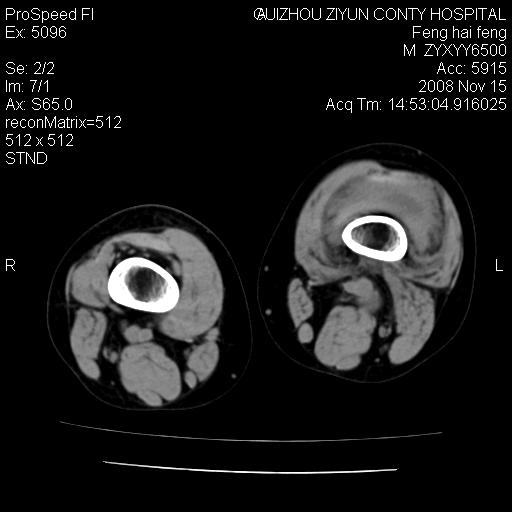

标题: CT16656:M 14Y 左膝关节肿胀一年余。其余病史不详。 [打印本页]

标题: CT16656:M 14Y 左膝关节肿胀一年余。其余病史不详。

考虑左侧髌骨结核;左膝关节滑膜肿胀、增厚,关节囊积液。

左膝滑膜型关节结核可能性大!支持!滑膜型关节结核主要ct表现:关节囊肿胀,积液,关节面见小破坏灶,并见点状死骨!

好大的左腿!考虑左侧髌骨结核,左膝关节滑膜肿胀、增厚,关节囊积液。

左侧髌骨结核;左膝关节滑膜肿胀、增厚,关节囊积液